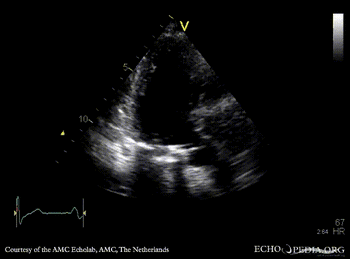

E00600.gif E00601.gif

A3CH A3CH with Color Doppler